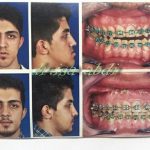

– متخصص جراحی فک , پلاستیک صورت و بینی

جراحی فک , پلاستیک , صورت وبینی

جراحی ترمیمی و زیبایی فک و صورت و جمجمه و گردن

چه افرادی نیاز به جراحی فک دارند؟

صورتشان از روبهرو و پهلو تقارن ندارد.

در جویدن و گاز زدن مشکل دارند.